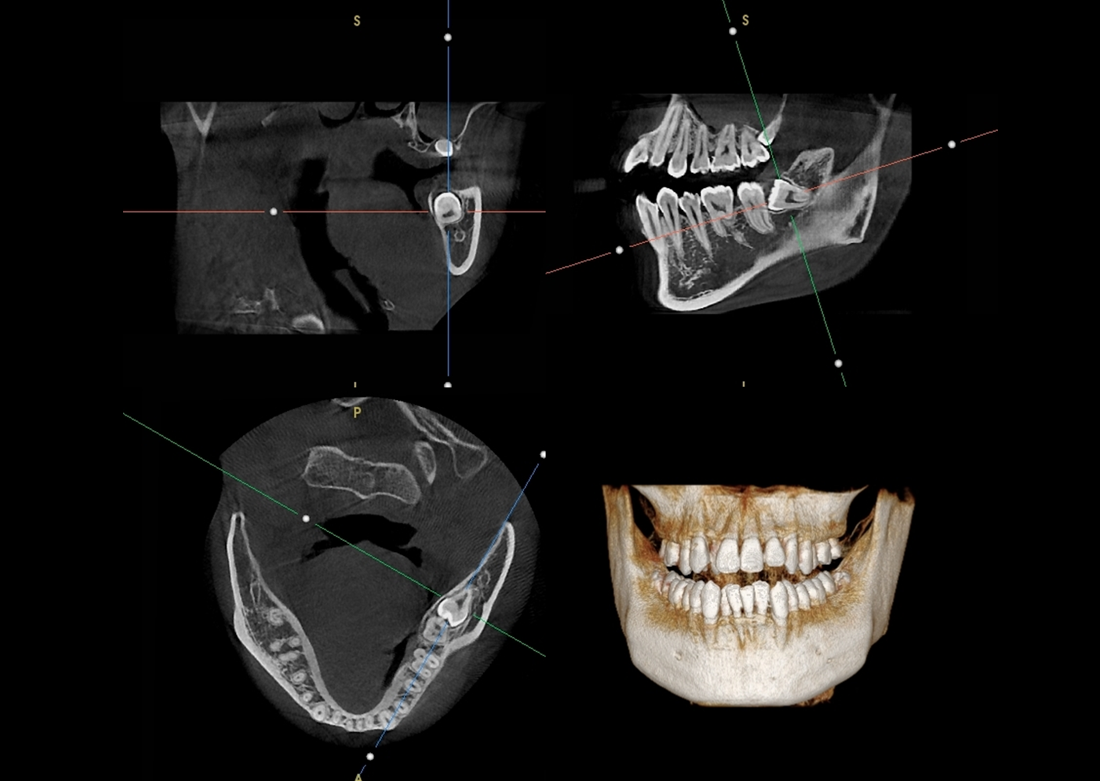

KLİNIKAI KÉPEK

Kiváló diagnosztikai képalkotás több éves tapasztalattal és szakértelemmel.

A Genoray büszkesége, amelyet világszerte elismernek és szeretnek.